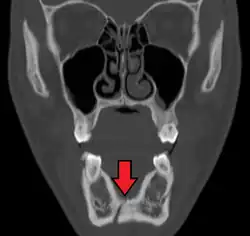

Computed tomography

Computed tomography is the most sensitive and specific of the imaging techniques. The facial bones can be visualized as slices through the skeletal in either the axial, coronal or sagittal planes. Images can be reconstructed into a 3-dimensional view, to give a better sense of the displacement of various fragments. 3D reconstruction, however, can mask smaller fractures owing to volume averaging, scatter artifact and surrounding structures simply blocking the view of underlying areas.

Research has shown that panoramic radiography is similar to computed tomography in its diagnostic accuracy for mandible fractures and both are more accurate than plain film radiograph.[12] The indications to use CT for mandible fracture vary by region, but it does not seem to add to diagnosis or treatment planning except for comminuted or avulsive type fractures,[13] although, there is better clinician agreement on the location and absence of fractures with CT compared to panoramic radiography.[14]